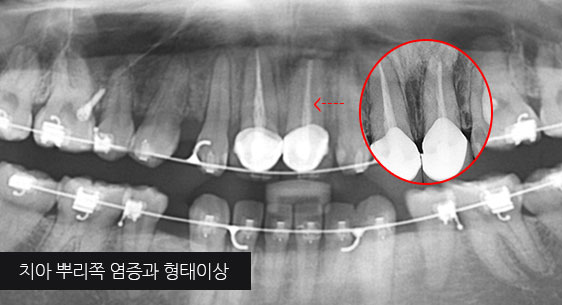

대부분의 치과에선 빼야하는 치아가 있거나 이미 빠졌거나, 신경 치료 후 예후 불량으로 인해 치아를 살릴 수 없는 경우 임플란트를 먼저 고려합니다.

고운미소치과는 인접치아를 움직여 그 공간을 닫아 임플란트 수술이나 보철 치료 없이 자연치를 최대한 활용하는 치료 계획을 세웁니다.

치조골 손상이 심해 발치를 하고 임플란트를 해야 하는 상황

인접치아로 발치된 공간을 메움

자연치보존 교정치료